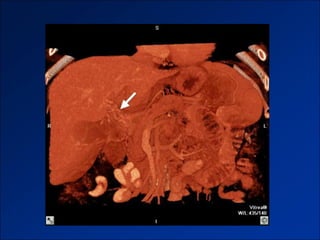

1. Gan biến đổi hình thái và đường bờ

1. Gan biến đổi hình thái và đường bờ (thể nốt lớn)

1. Gan biến đổi hình thái và đường bờ (thể nốt nhỏ)

1. Gan biếnđổi hình thái và đường bờ

1. Gan biếnđổi hình thái và đường bờ (thể nốt lớn)

1. Gan biếnđổi hình thái và đường bờ (thể nốt nhỏ)